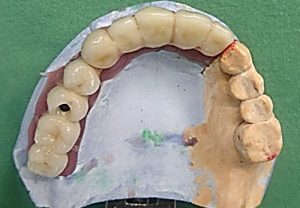

2. PHASE – state before making immediate impressions

3. PHASE – prosthetic fabrication of temporary crown on implant

3. PHASE – fabrication of temporary solution